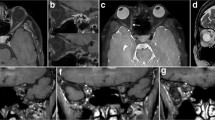

On axial T2-weighted MRI performed in the initial examination, the central part of some intraorbital ONs was delineated as a well-demarcated linear hyperintense area (Fig. 2). The finding was identified in 17 of 89 patients (19%), 9 on the right side and 11 on the left side. On the thin-sliced serial coronal images, hyperintense areas were identified on both sides in 81 patients (91%). They were delineated as continuous hyperintense areas in the ONs with an inconsistent appearance even in the same nerve, from the orbital apex to its tip. In 11 patients (12.4%), the areas were divided into upper and lower parts by a horizontal septum, 9 on the right and 10 on the left. Other patients had hyperintense areas in the ONs with variable morphologies, lacking a septum (Fig. 3). These areas involved the central part of the ON and showed highly interindividual variability (Fig. 4). Furthermore, on the thin-sliced sagittal images, hyperintense areas were identified in 41 patients (46%), 30 on the right and 28 on the left, in variable parts of the intraorbital ONs (Fig. 5).

The identification rates of the hyperintense areas are summarized in Table 1.